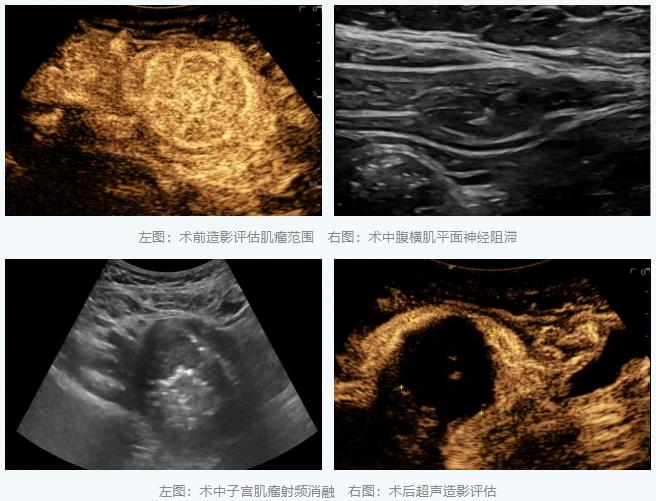

另一位女性患者因巨大子宫肌瘤(约70×55×55毫米)导致严重经量增多和压迫症状。此类肌瘤消融时间较长,单纯局麻术中疼痛明显。为提升治疗体验,团队创新性地采用了“超声引导下腹横肌平面神经阻滞联合局部浸润麻醉”的方案。

在超声直视下,李彦青主任医师将麻醉药物精准注射到支配手术区域的神经周围,实现了高效的区域镇痛。在整个长达40多分钟的消融过程中,患者生命体征平稳,无明显痛感,第二天出院。这种麻醉方式避免了全身麻醉的风险,显著减轻了术后疼痛,减少了镇痛药用量,真正体现了“以患者为中心”的舒适化医疗理念。